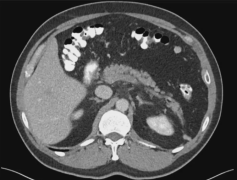

Simple Hepatic Cyst 单纯性肝囊肿 单纯性肝囊肿是相对于复杂性肝囊肿而言(complex hepatic cyst) 单纯性肝囊肿通常是壁薄的囊性中午,其内部充满液体且有上皮细胞衬里。它们由胚胎发育期间出现的异常胆管细胞形成。如今,超声检查(US)、CT 和 MRI 等诊...